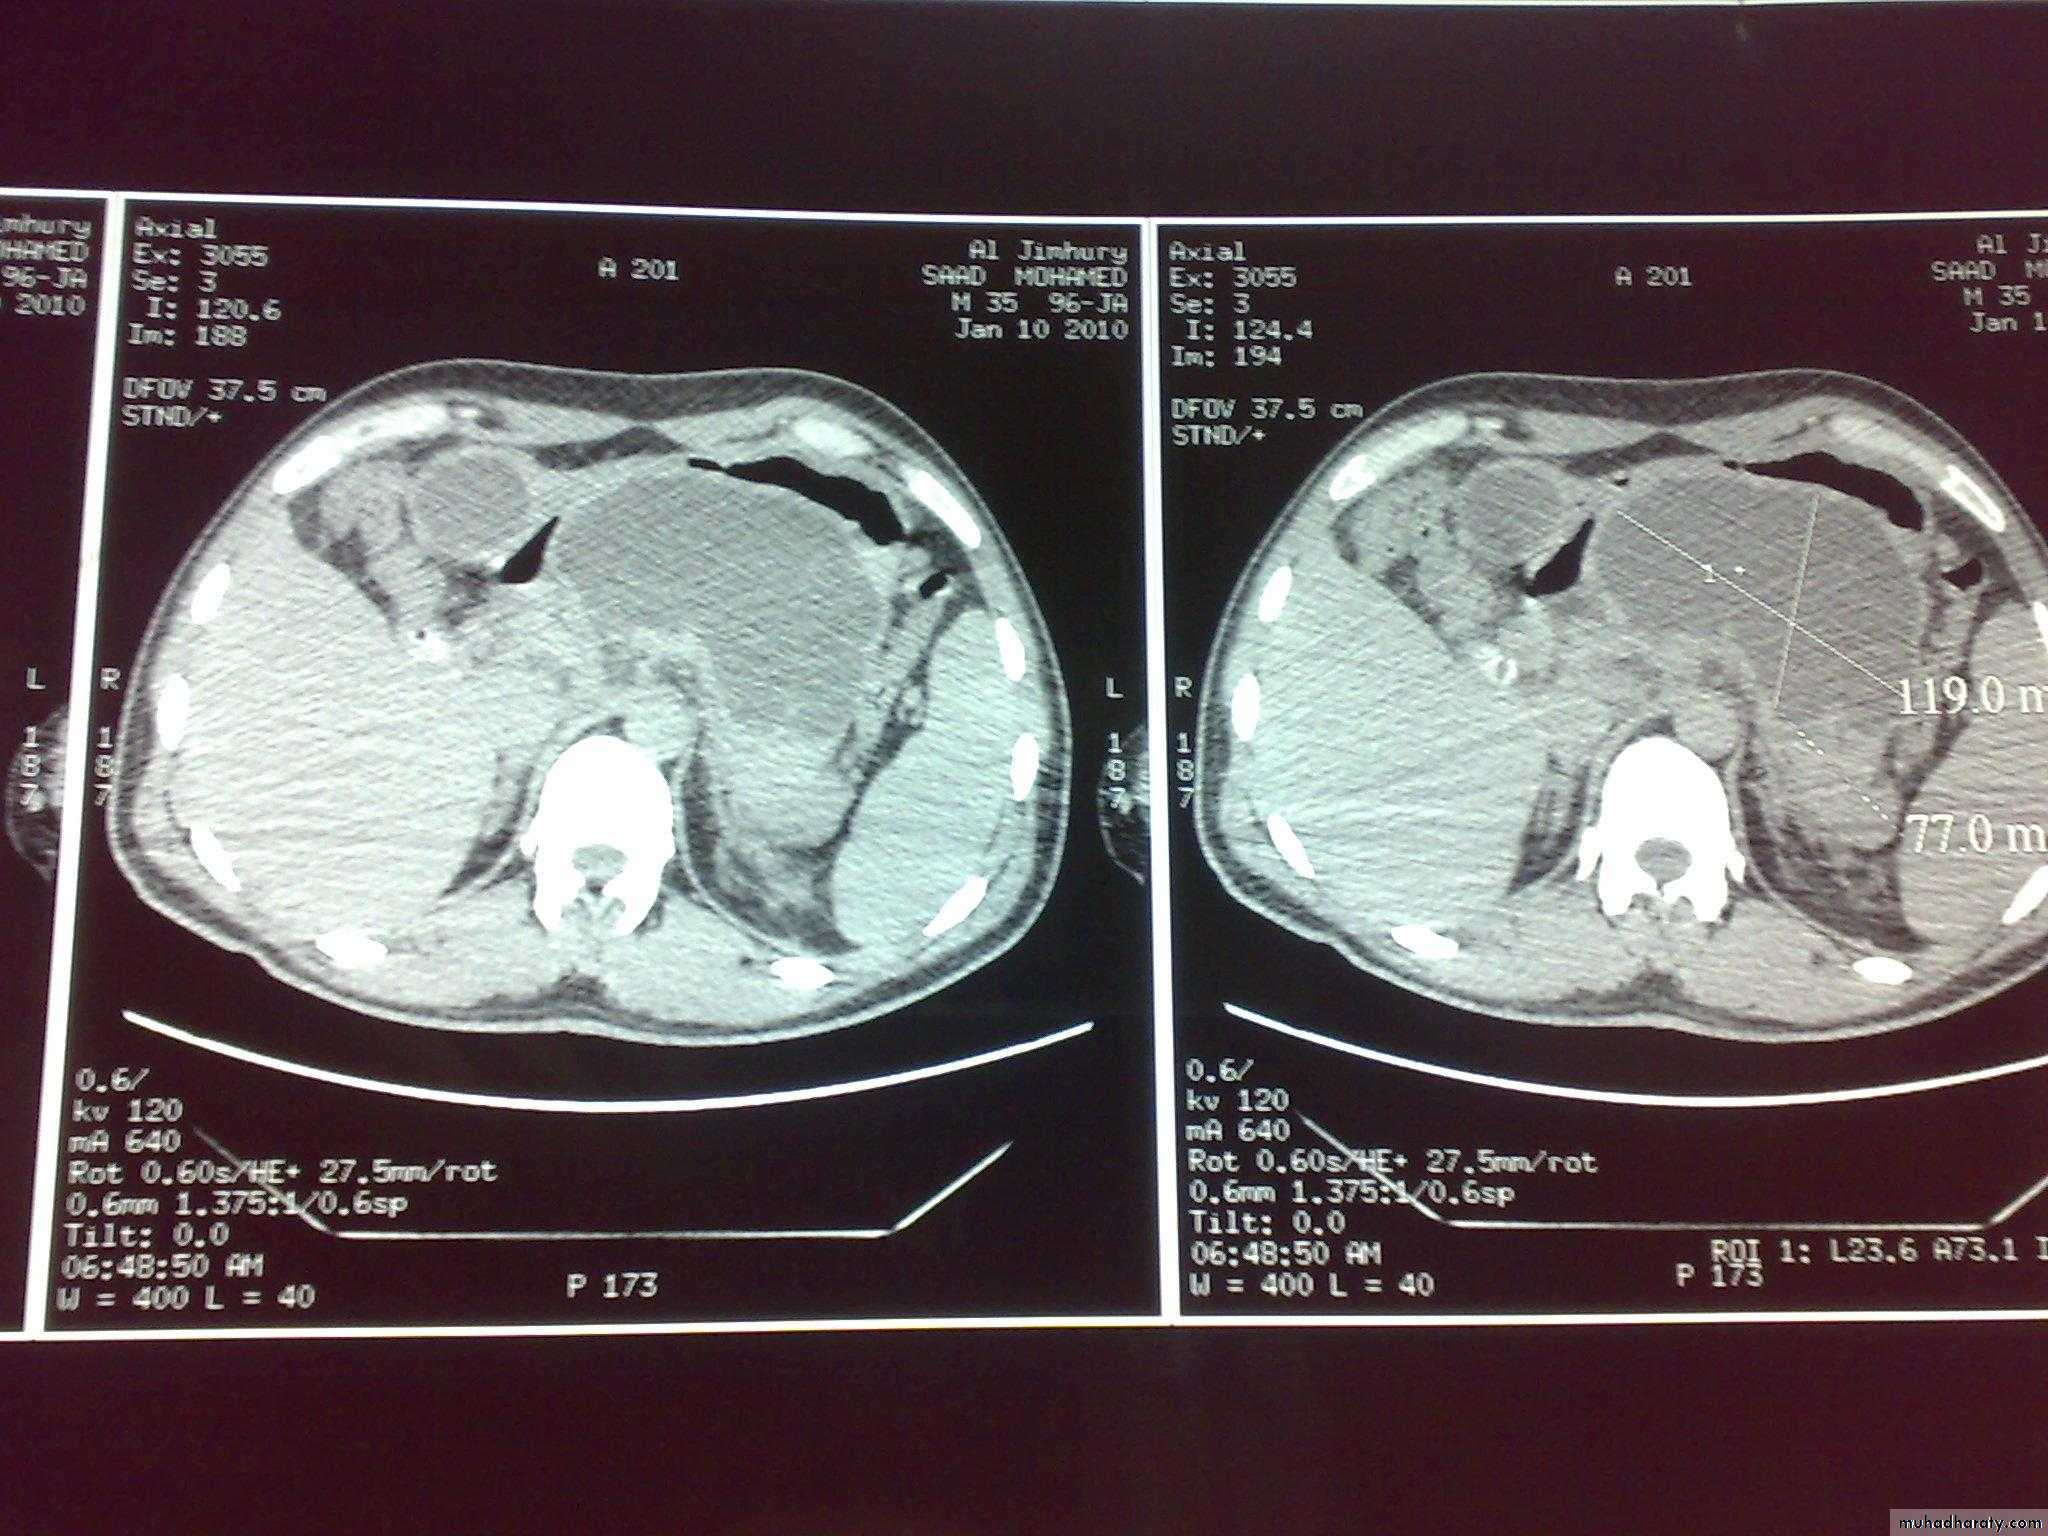

INVESTIGATIONS 1.SERUM AMYLASE ELEVATE WITHIN FEW HOURS>1000 IU/DL. NR 100-300 2.ARTERIAL BLOOD GASES 3.BIOCHEMICAL .BILIRUBIN ELEVETED.HYPOCAL.HYPOPROT.ELEVETED B.UREA.HYPERGL. 4.BLOOD PICTURE .LEACOCYTOSIS.ELEVATED HAEMATOCRIT 5.U/S GALL STONES, SWOLLEN EDEMATOUS PANCREAS 6.PLAIN X-RAY OF ABDOMEN SHOWS DILATED SHORT SEGMENT OF SMALL INTESTINE(SENTINEL LOOP).COLON CUT-OFF SIGN, RENAL HALO SIGN7.CT VERY HELPFUL SHOWS ENLARGEMENT OF PANCREAS,OEDEMA ,NECROSIS. 8.ECG &CARDIAC ENZYME TO EXCLUDE M.I

PANCREATIC PSEUDOCYST COLLECTION OF PANCREATIC SECRETION &INFLAMMATORY EXUDATE WITHIN A LINING OF INFLAMMATORY TISSUE AETIOLOGY DEVELOPS IN 10% OF CASES OF ACUTE PANCREATITIS AFTER 4 WEEKS.NEXT CAUSE PANCREATIC TRAUMA SITE LESSER SAC COMPLICATIONS INFECTION ,HAEMORRHAGE,RUPTURE CLINICAL FEATURES -SMALL PAINLESS DISCOVERED BY U/S -LARGE CAUSE DISCOMFORT ,UPPER ABD. SWELLING INVESTIGATIONS -BA-MEAL FORWARD DISPLACEMENT OF STOMACH -U/S&CT